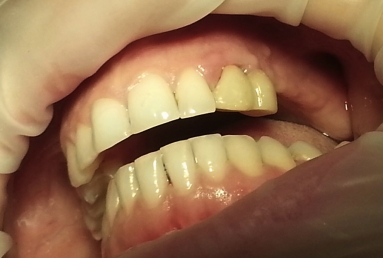

Initial situation: the patient had a an incorrect bridge for five years in the left maxillary area, this caused the extraction of the posterior tooth that was sustaining the bridge together with the wisdom tooth then three implants were inserted in the maxillary bone.

After the osseointegration of the implants three porcelain and zirconium crowns were made. At the same time full ceramic crowns were made for the left canine and the two right premolars, which had deep cavities and needed root canal treatment.

Before starting the prosthetic treatment, the patient wanted a tooth bleaching using the whitening lamp to activate the gel, so the final color for the crowns was chosen according to the color obtained after the whitening.